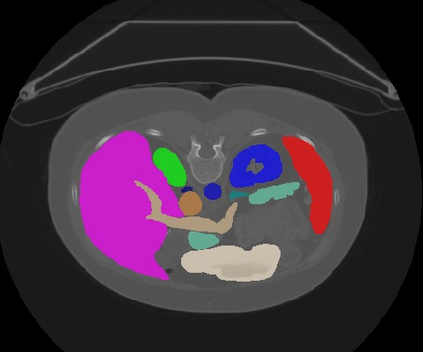

Transformers, the default model of choices in natural language processing, have drawn scant attention from the medical imaging community. Given the ability to exploit long-term dependencies, transformers are promising to help atypical convolutional neural networks (convnets) to overcome its inherent shortcomings of spatial inductive bias. However, most of recently proposed transformer-based segmentation approaches simply treated transformers as assisted modules to help encode global context into convolutional representations without investigating how to optimally combine self-attention (i.e., the core of transformers) with convolution. To address this issue, in this paper, we introduce nnFormer (i.e., Not-aNother transFormer), a powerful segmentation model with an interleaved architecture based on empirical combination of self-attention and convolution. In practice, nnFormer learns volumetric representations from 3D local volumes. Compared to the naive voxel-level self-attention implementation, such volume-based operations help to reduce the computational complexity by approximate 98% and 99.5% on Synapse and ACDC datasets, respectively. In comparison to prior-art network configurations, nnFormer achieves tremendous improvements over previous transformer-based methods on two commonly used datasets Synapse and ACDC. For instance, nnFormer outperforms Swin-UNet by over 7 percents on Synapse. Even when compared to nnUNet, currently the best performing fully-convolutional medical segmentation network, nnFormer still provides slightly better performance on Synapse and ACDC.